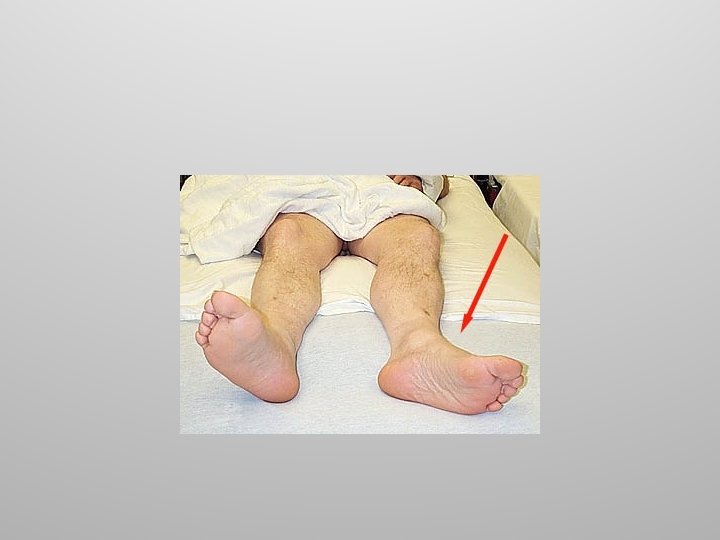

Hip Injuries Common injuries to the hip joint include fractures and dislocations. Hip fractures typically involve the neck of the femur and are the result of underlying disease such as osteoporosis.